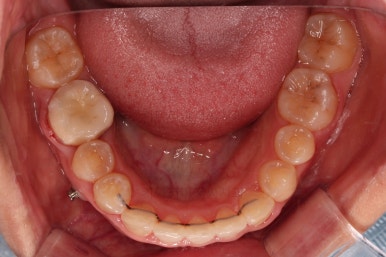

오늘 소개해 드릴 환자분은 아래 앞니가 하나 없는 결손치아, 그로 인해서 윗니 앞니가 뒤로 굽어 들어오는 "옥니", 그로 인해 위아래 앞니가 많이 겹치는 과개교합 및 잇몸웃음(거미스마일)이 나타나는 복합적인 문제가 있는 분이셨습니다.

문제의 시작은 바로 아래 앞니였어요.

맨 아래 오른쪽 사진에 화살표를 보시면 앞니가 4개여야 하는데 3개 밖에 없네요.